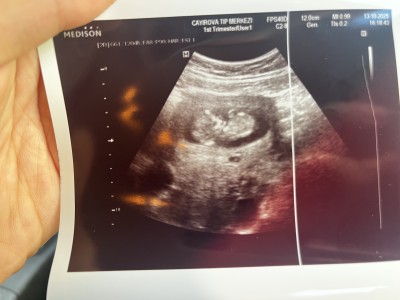

Kızlar 11+

imageKızlar 11+4 teyiz doktor çok erken dedi ama bir tahminim var dedi sizin var mı anlayan varsa yorumlayabilir mi

Gebelik haftası 11+4

İlk fotoda mı öyle hissettin 2. De mi bende ilkte kız ikincide erkeğe benzettim amin inşallah

Yok yapısından baktim daha narin kafası vucuduyla eşit gibi . İkincide de zaten bacak arası görünmüyor ki